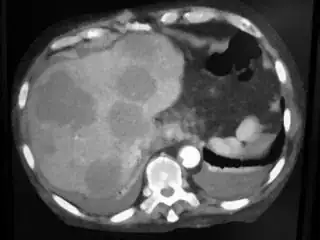

Below are some of the opened and segmented images. Of course there's more to be done in terms of

- separating out the liver region

- generalizing this to a large dataset

but hope this is at least a starting point.

You might be able to narrow down the region or interest by filtering out the darkest and the lightest regions from the segmented image. For this, use the k-means cluster centers, check for the extreme values (max and min) and remove the corresponding k values from the labeled image. Then you can look for large structures to the left of the result image. Worst case, you might get a hole on the left side when the extreme region filtering goes wrong. I've updated the code and results.